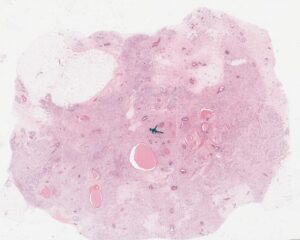

Macroscopía de tumor de mama